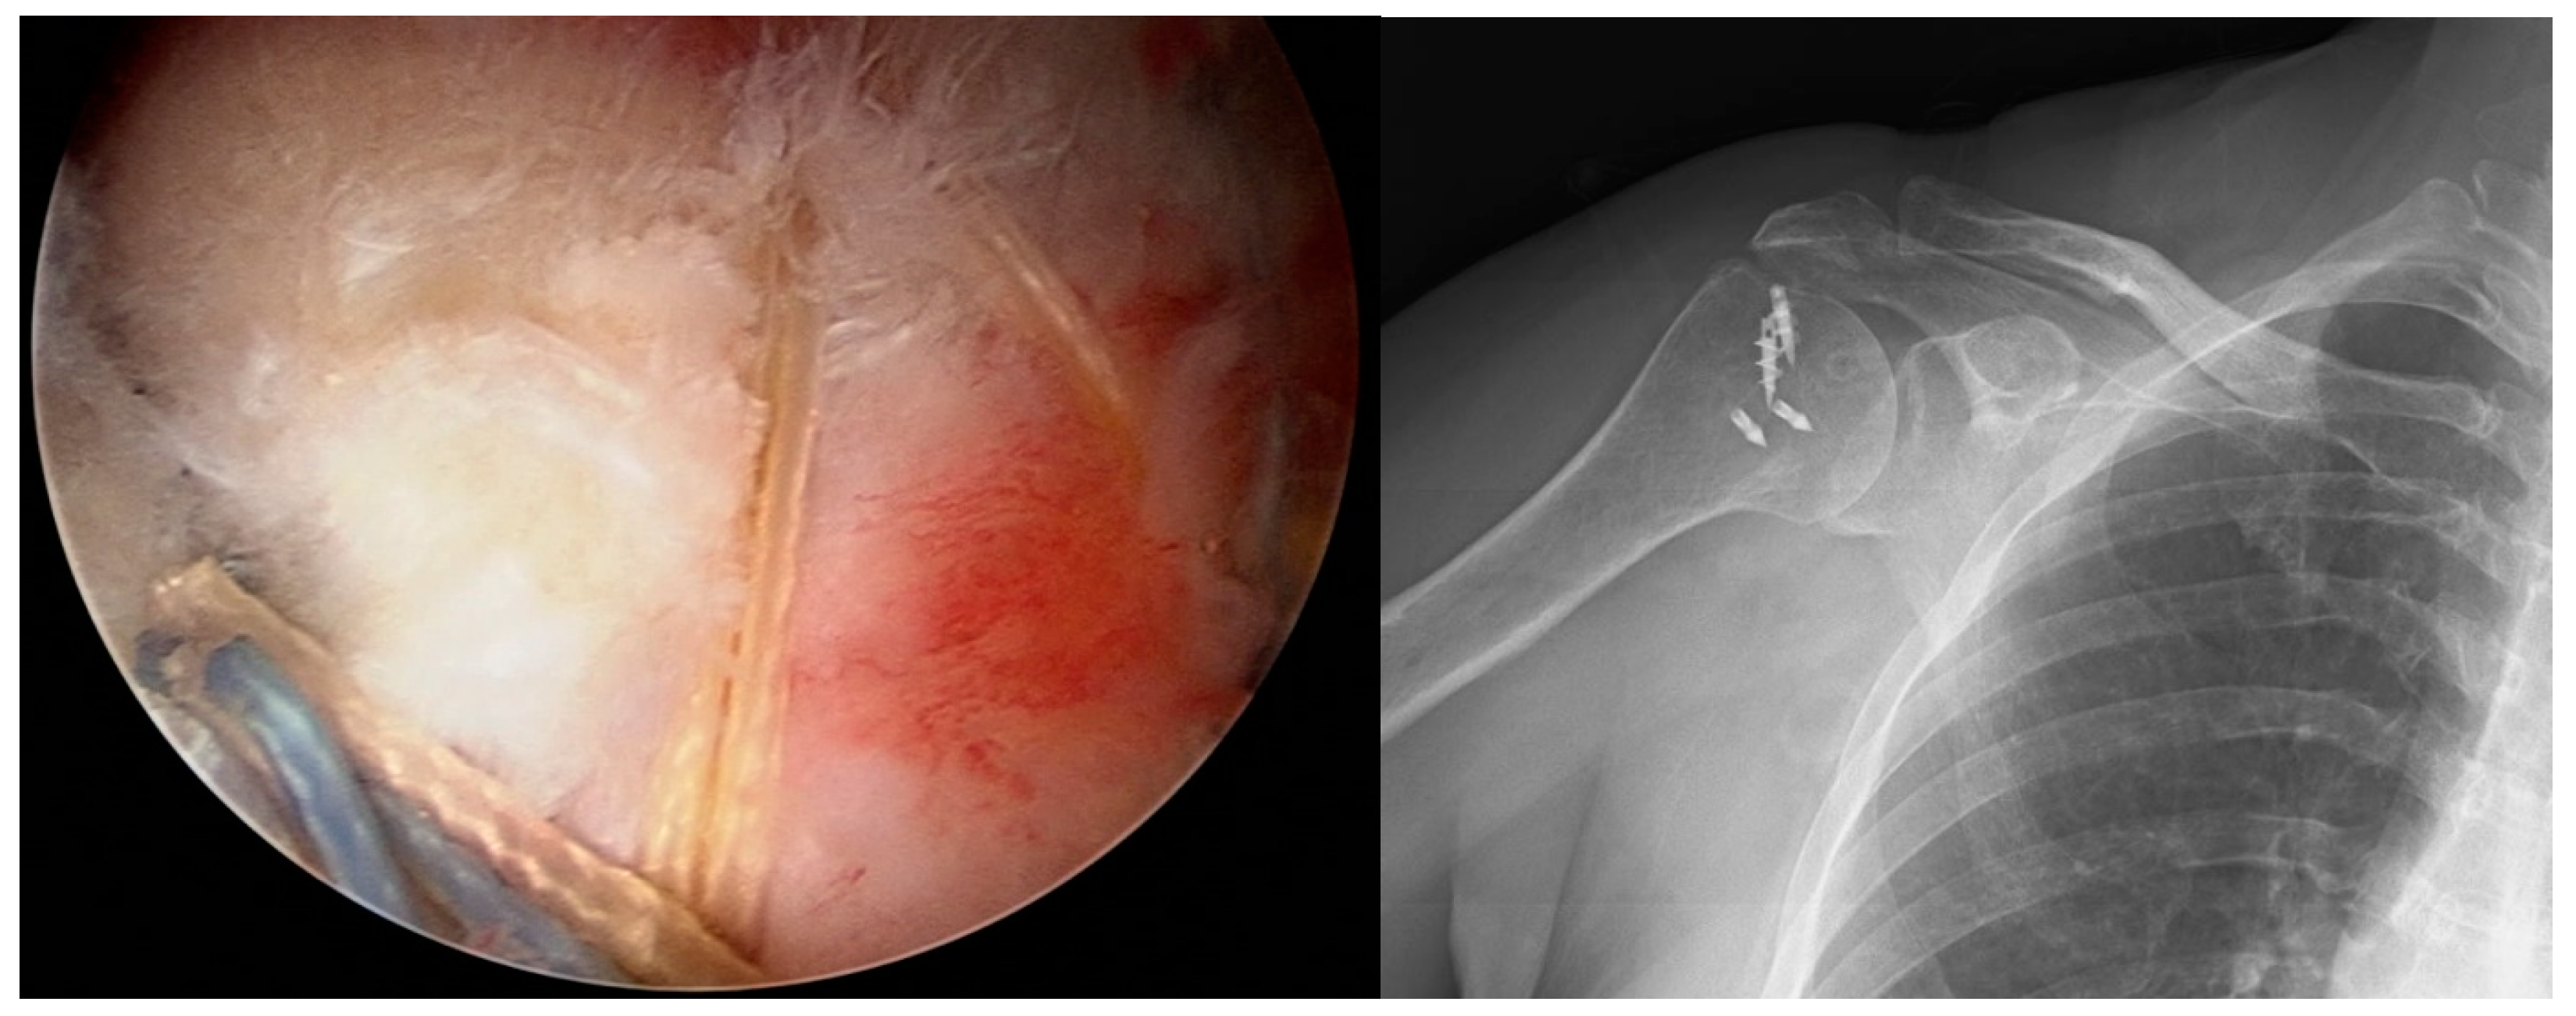

2.1. Surgical Procedure